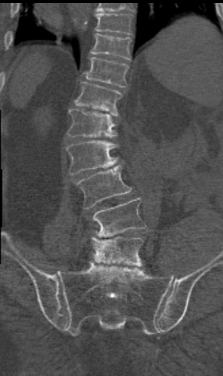

Hoewel Adolescenten Idiopathische Scoliose (AIS), de vorm die vooral optreedt bij verder kerngezonde meisjes in de puberteit, nog altijd de meest voorkomende soort scoliose is, komt scoliose op de volwassen leeftijd steeds meer voor, en veroorzaakt vaak heftige klachten (Figuur 1). Deze vorm wordt vaak ‘degeneratieve scoliose’ of in het Engels ‘Adult SpinalDeformity (ASD)’ genoemd, en doet zich vooral voor in het onderste deel van de wervelkolom, de lenden wervelkolom (lumbale wervelkolom, lwk).

Vervolgens moet bij het lichamelijk onderzoek opnieuw een indruk worden verkregen van de algemene vitaliteit en gezondheid van de betrokkene, er moet worden gekeken naar de functie van de rug, de aard, intensiteit en plaats van de pijn, en of er aanwijzingen zijn voor permanent beklemde zenuwen. Bij neurogene claudicatio zal dat dus in het algemeen NIET het geval zijn, deze zenuwen raken pas geïrriteerd en geven pijnsignalen af bij het lopen. Daarnaast moet worden gekeken naar de functie van de heupen, de knieën en de bloedvaten in de benen. Hiermee is in het algemeen al een belangrijk deel van de diagnose duidelijk geworden, het nog volgende onderzoek is vooral een aanvulling op het inmiddels verkregen plaatje. Hoe gerichter de vraagstelling is bij het maken van foto’s en eventuele scans, hoe meer kans dat deze ook belangrijke aanvullende informatie opleveren. Vaak zal behoefte bestaan aan röntgenfoto’s van de gehele rug, eventueel de heupen en de knieën, en in sommige gevallen een MRI-scan of CT-scan van de onderrug.